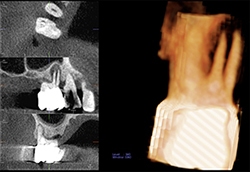

超低被ばく線量のKaVo社製のCBCTを導入しています。このCT装置は、エックス線のパルス照射により、患者様の被ばく線量を最小限に抑えます。